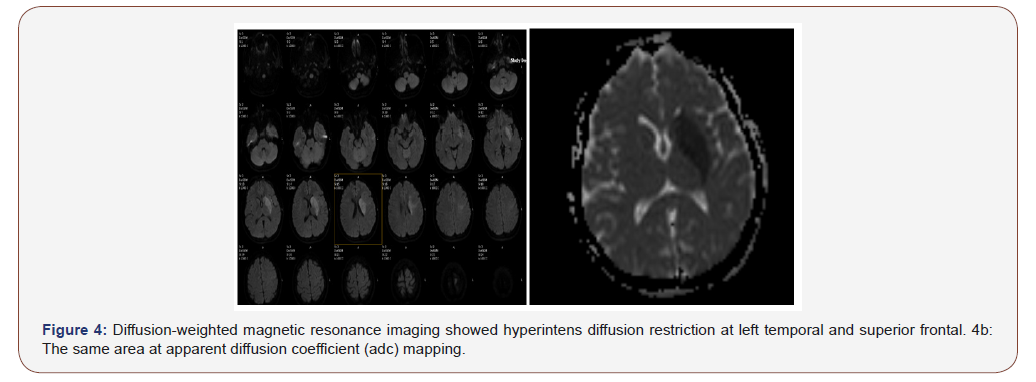

Contrast-enhanced brain magnetic resonance imaging revealed a left temporal and superior frontal subacute infarct (Figure 3), diffusion-weighted magnetic resonance imaging showed hyperintense diffusion restriction at the same area (Figure 4a and 4b). Magnetic resonance venography (MRV) of the brain revealed extensive sub-acute transverse sinus thrombosis (Figure 5). Doppler ultrasonography did not show any lesion on cervical arteries. Transthoracic and transesophageal cardiac ultrasound excluded thrombus or cardiac abnormalities.